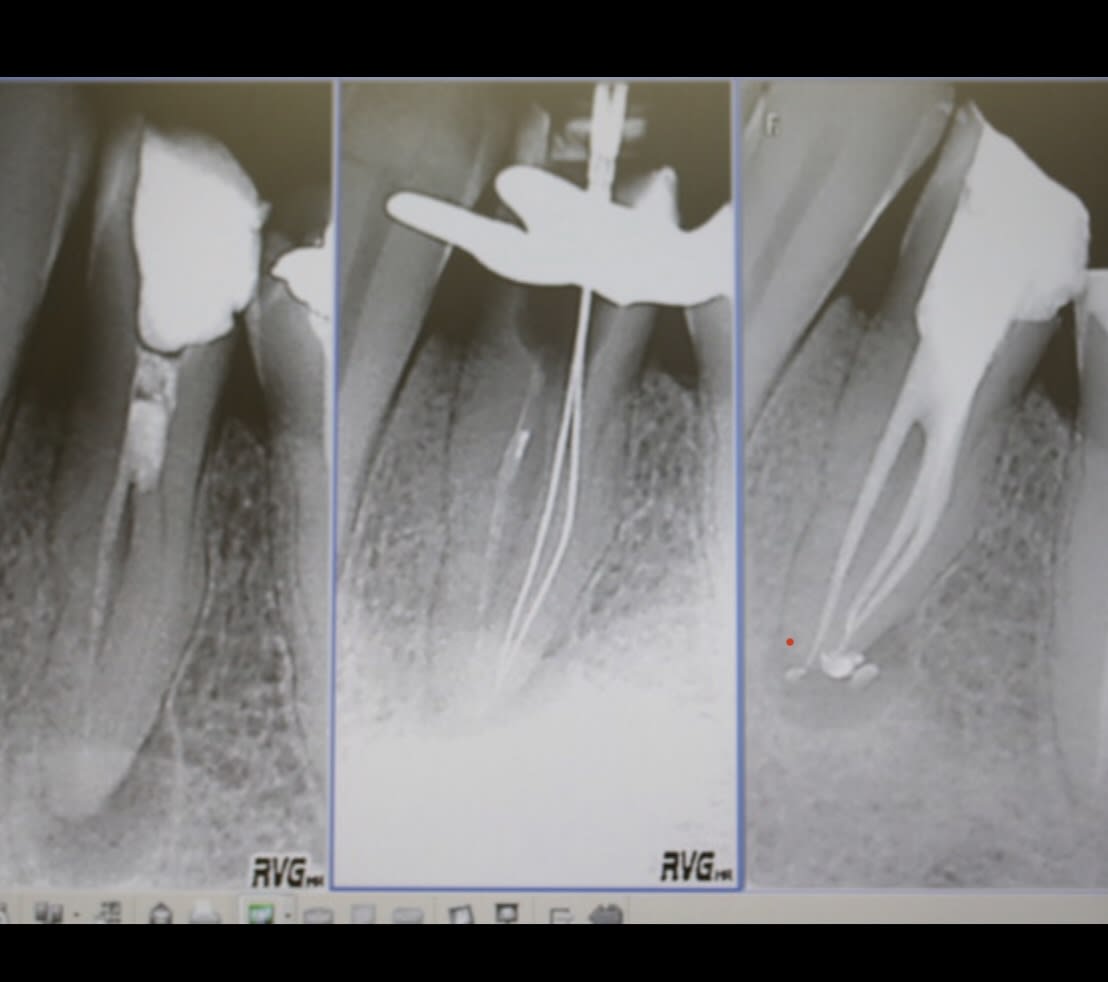

les Rx sont pas top, mais au final mon standard c'est ça.

J'ai repris la 5 ensuite.

Rob 1 ffmwtf - Eugenol

Rob 2 ou8kl6 - Eugenol

Rob 3 fgapwa - Eugenol

Celle là, j'aurai peut-être dû adresser, parce qu'à l'apex il y a probablement plus de ciment que de gutta, mais c'est pas si mal, avec du temps...

C'est en radiologie que je devrais me former:-)